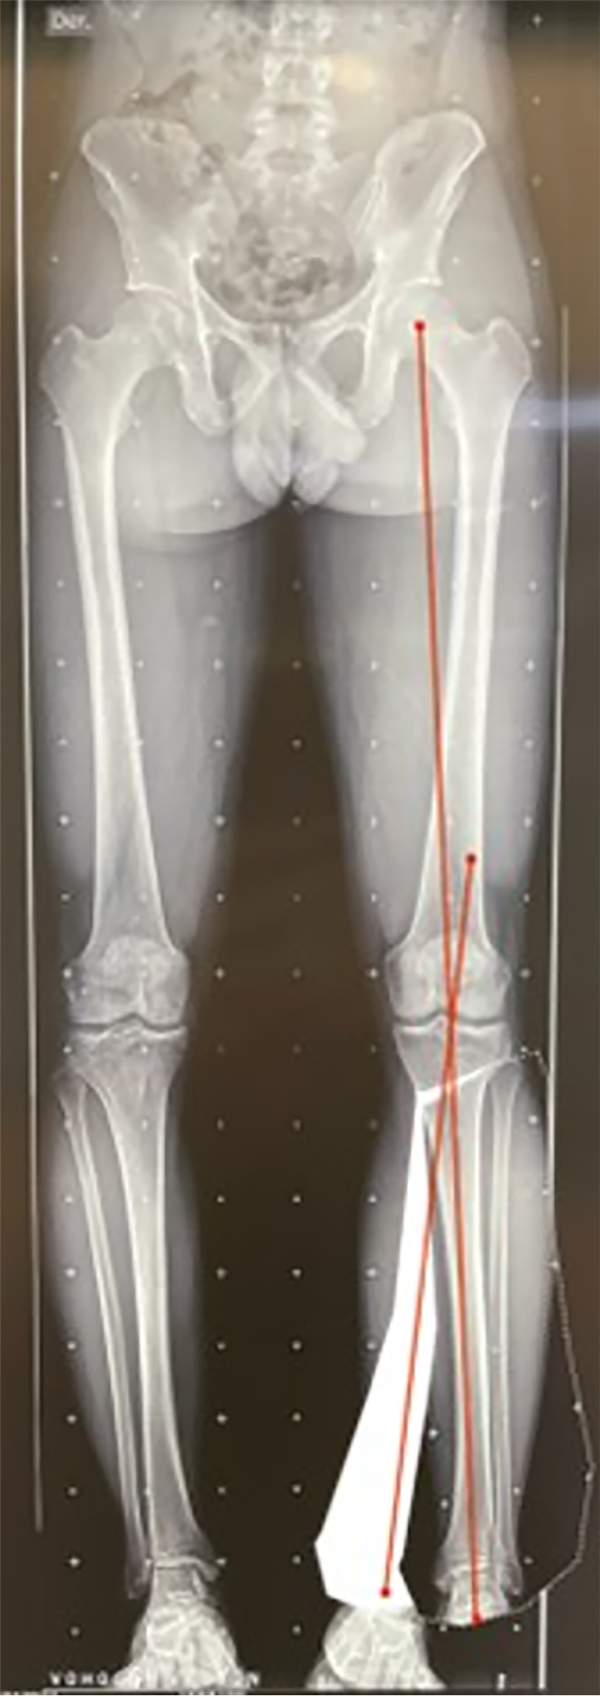

El paso 0 consiste en trazar una línea que va del centro articular de la cadera al centro articular del tobillo, recibe el nombre de “eje mecánico del miembro inferior” y el resultado fisiológico de esta medición es una línea que debe cruzar el centro articular de la rodilla con un rango de normalidad de desviación de 3 mm hacia medial o lateral.10 Al realizar la medición de la desviación, esta medida va a recibir el nombre de desviación del eje mecánico (MAD, por su nombre en inglés), según el cual, en caso de superar los 3 mm hacia medial, se trata de una deformidad en varo con un aumento de la carga en el compartimento medial de la rodilla; cuando el MAD se encuentra superior a los 3 mm laterales, es una deformidad en valgo y aumenta la carga del compartimento lateral de la rodilla21 (fig. 3).

Figura 3: Test de mal alineamiento: las líneas rojas corresponden al eje mecánico de los miembros inferiores, se marca el centro articular de la rodilla y se observa la desviación del eje mecánico o MAD derecho hacia medial de 24 mm, y en el izquierdo de 31 mm hacia medial, se evidencia una alteración de este valor con una deformidad en varo bilateral, con mayor predominio del lado izquierdo.